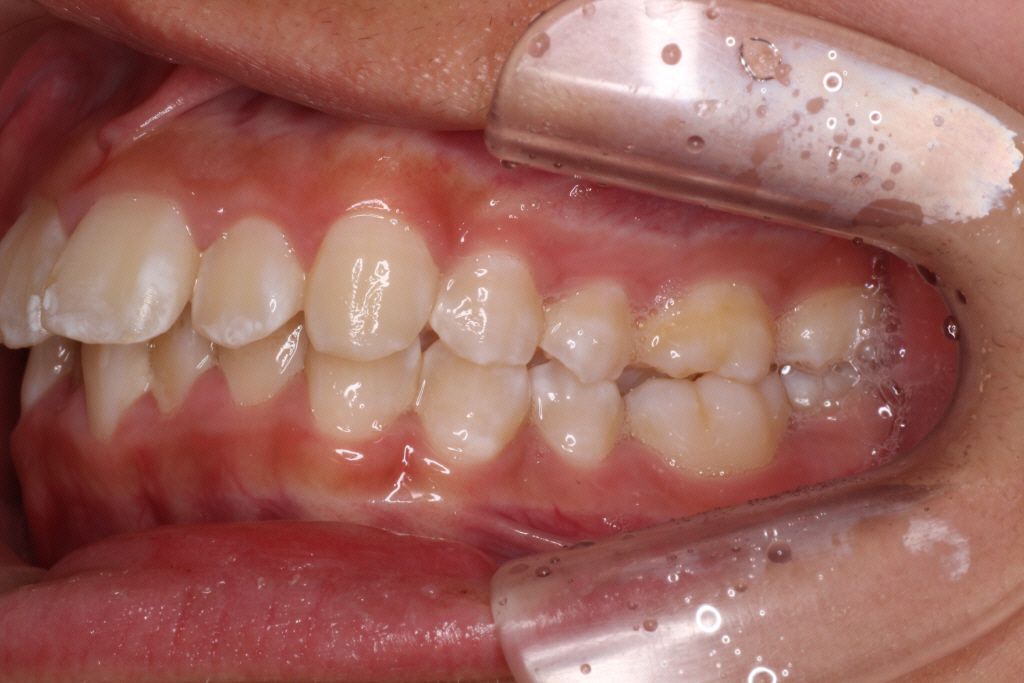

カリエールモーションが終わった時の口腔内写真です。

上の奥歯が後ろに下がったおかげで前歯には隙間ができています。

左の噛み合わせを見ると下の歯と歯の間に上の歯が入り込んでいることがわかります。

1歯対2歯の関係です。

右の噛み合わせを見ると左の噛み合わせより少し多めに奥歯を後ろに下げていることがわかります。

オーバーコレクションといって少し戻ることを想定して多めに動かしておくことを言います。